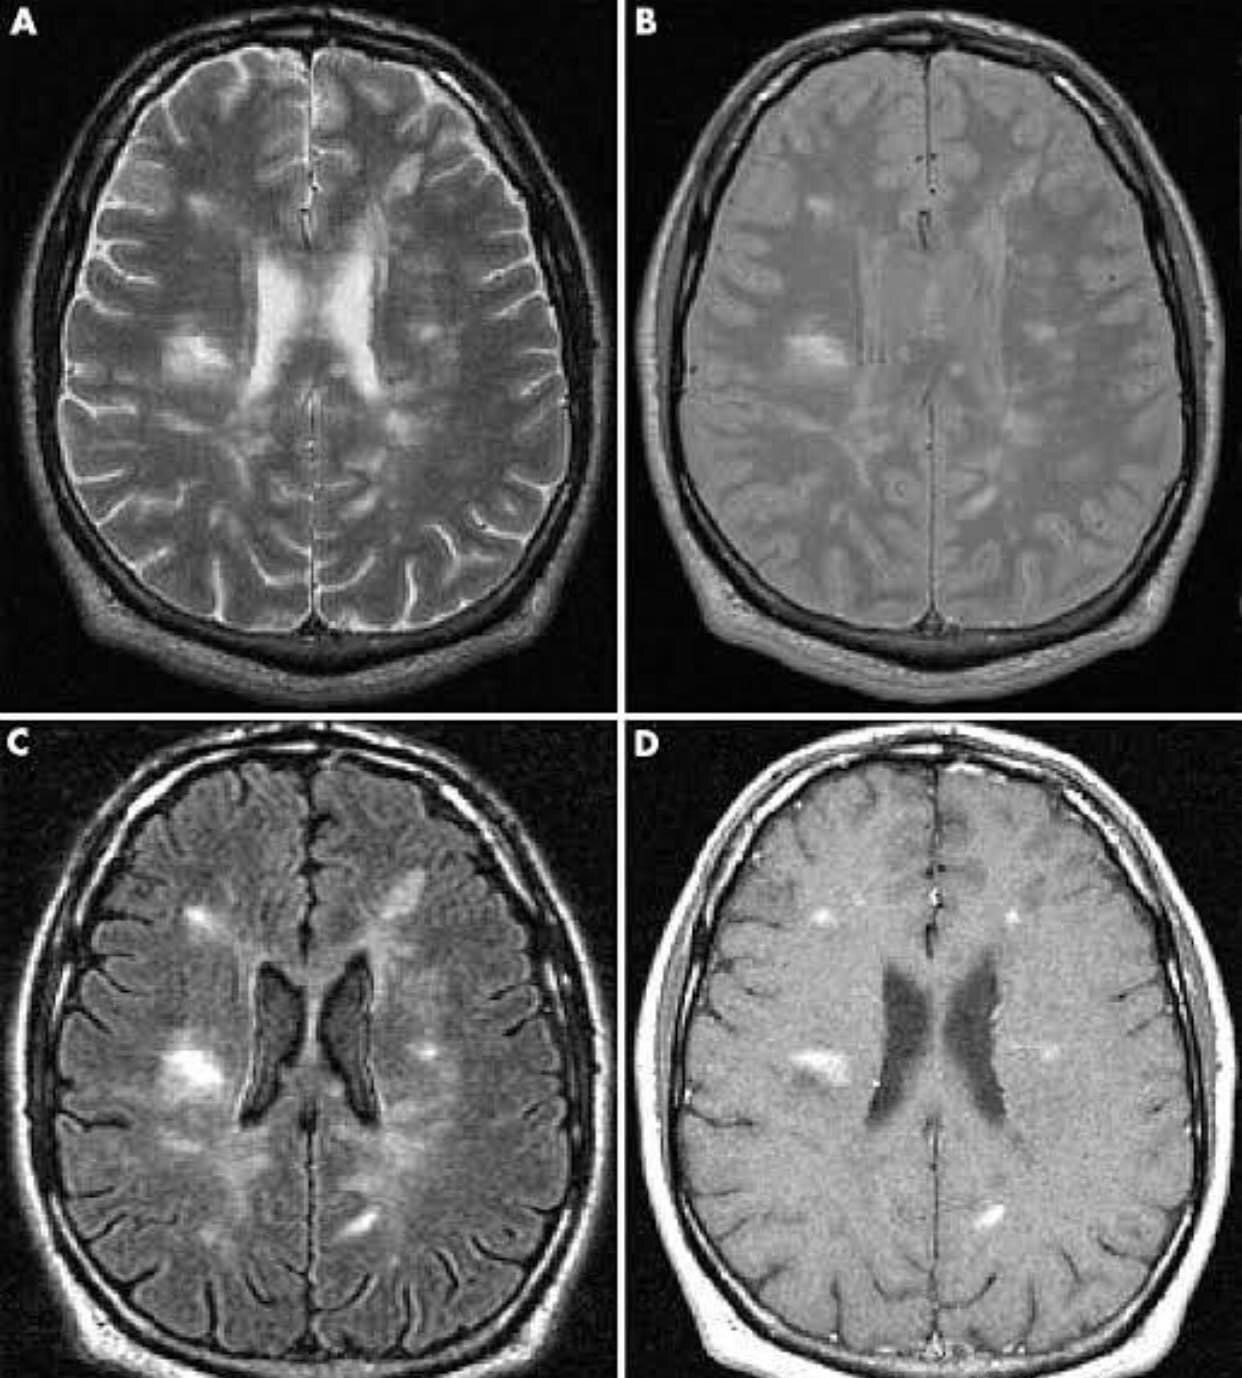

Multiple sclerosis (MS) is a relatively common acquired chronic relapsing demyelinating disease involving the central nervous system, and is the second most common cause of neurological impairment in young adults, after trauma 19. Characteristically, and by definition, multiple sclerosis is disseminated not only in space (i.e. multiple lesions in different regions of the brain) but also in time (i.e. lesions occur at different times). A number of clinical variants are recognised, each with specific imaging findings and clinical presentation. They include: - Classic multiple sclerosis (Charcot type) - Tumefactive multiple sclerosis - Marburg type (acute malignant) - Schilder type (diffuse cerebral sclerosis) - Balo concentric sclerosis Clinical presentation is both highly variable acutely, as a result of varying plaque location, as well as over time. Examples of common clinical features include: Brainstem and cranial nerve involvement: - optic neuritis - internuclear ophthalmoplegia (often bilateral) - trigeminal neuralgia - diplopia (e.g. due to abducens nerve palsy) - vertigo Cerebellum involvement: - ataxia and gait disturbance - oscillopsia Cerebrum and spinal cord involvement: - limb sensory loss or paraesthesias - upper motor neurone signs - Lhermitte sign - urinary incontinence Others: - fatigue - depression - cognitive decline [ Via Medicos ]